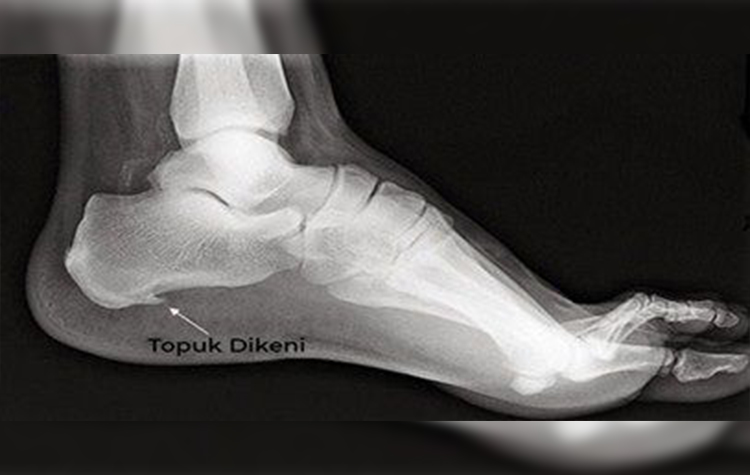

Bazı cilt sorunlarının topuk dikeni ile karıştırıldığını belirten Dr. Dinç, sözlerine şöyle devam etti: “Topuk dikeni, esasında topuk kemiğinin alt veya arka kısmında kalsiyum birikmesi sonucu ortaya çıkan kemiksi çıkıntıya denir. Kemik-kas bileşke yerinde olduğu için dışarıdan gözükmez. Halk arasında topuk bölgesinde görülen deri sertlikleri, çıkıntıları ve siğillerine de topuk dikeni deniliyor. Bunların topuk dikeni ile ilgisi olmayıp, cildiye doktoru tarafından değerlendirilmeleri ve tedavi edilmeleri gerekir. Topuk dikeni genellikle ayağın altında bulunan plantar fasya denilen kalın doku bandının iltihaplanması sonucunda ortaya çıkar. Bu doku bandı şok emici bir kemer gibi davranarak ayağı destekler. Bu banttaki stres ve gerginlik arttığında zamanla iltihaplanma gelişir ve bölgede kalsiyum birikmeye başlar. Bu birikim röntgende kolayca tespit edilebilir.”